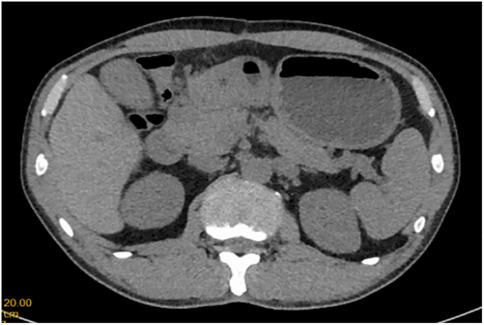

A 51-year-old male patient was admitted to the Department of Gastrointestinal Surgery in September 2020, presenting with “melena for one week and sudden abdominal pain for 11 h”. The patient had no significant medical history. Physical examination revealed right upper abdominal muscle tension, accompanied by tenderness and rebound pain in the same region. Laboratory tests indicated severe anemia (hemoglobin: 57 g/L), while tumor markers, including alpha-fetoprotein (AFP), carcinoembryonic antigen (CEA), carbohydrate antigen 199 (CA199), and carbohydrate antigen 724 (CA724), were within normal ranges. Computed tomography (CT) findings suggested gastrointestinal perforation. Consequently, the patient underwent surgical repair of a perforated duodenal bulb ulcer, followed by medical management with proton pump inhibitors. However, the patient failed to adhere to follow-up recommendations after discharge. In March 2021, the patient was readmitted due to “dizziness and fatigue for two days”. Laboratory tests revealed critically severe anemia (hemoglobin: 35 g/L). Gastroscopy demonstrated congested and erythematous gastric antral mucosa, pyloric deformity, and an ulcer on the anterior wall of the duodenal bulb with luminal narrowing, preventing endoscopic passage. Residual sutures and minor bleeding were observed (no biopsy was performed). Abdominal CT revealed thickening and irregularity of the gastric antrum and duodenal bulb walls, with no evidence of lymphadenopathy or masses (Figures 1, 2). Given the patient's recurrent duodenal bulb ulcer bleeding with stenosis and failure of conservative medical treatment, a laparoscopic distal gastrectomy (including resection of the bulb ulcer scar tissue) with gastrojejunostomy was performed. Postoperative pathological examination confirmed poorly differentiated adenocarcinoma in the anterior wall of the duodenal bulb, consistent with malignant transformation of the ulcer. The tumor, which measured 2.5 × 1.5 × 1.5 cm, is approximately 2 cm from the distal resection margin, with full-thickness invasion of the duodenal wall and extension into surrounding adipose tissue (Figures 3, 4). Intravascular cancer thrombi and perineural invasion were identified. Metastatic carcinoma was detected in six lymph nodes, and local mesenteric tissue infiltration was observed. Immunohistochemical staining results were as follows: CK7 (+), S-100 (nerve tissue +), CK20 (partially +), Ki67 (+ in approximately 45% of cells), Her-2 (−), and Villin (+). Mismatch repair proteins MLH1, MSH2, MSH6, and PMS2 were all expressed. Whole-body bone imaging showed no significant abnormalities. Postoperatively, the patient completed 8 cycles of CapeOX chemotherapy. Follow-up gastroscopy in September 2021 revealed multiple superficial ulcers in the isthmus and efferent loop. On May 13, 2024, follow-up gastroscopy identified an ulcer with stenosis in the isthmus (pathological biopsy confirmed no tumor recurrence), and abdominal enhanced CT showed no evidence of metastasis.